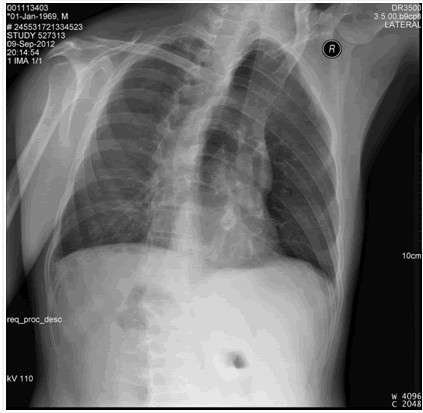

后肋骨折

圖示為右側3,5,6,7,8后肋骨折。